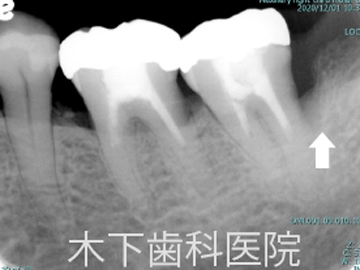

リグロスを用いた歯周組織再生療法症例

術前

歯周外科術前

術後3年

歯周外科術後